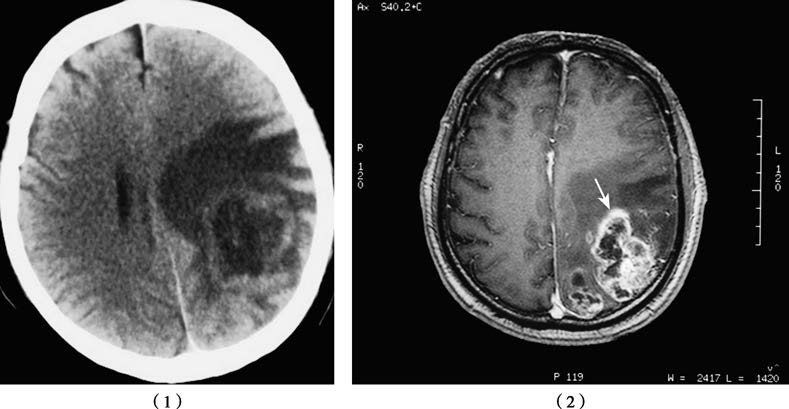

Figure 1 CT (1) and MR (2) images of a glioblastoma located in the left parieto-occipital region.

In head CT scans, high-grade gliomas often appear as hypodense or inhomogeneous lesions with prominent mass effect and peritumoral edema. On MRI, 90%–95% of these tumors exhibit significant inhomogeneous enhancement, with features such as cystic degeneration, hemorrhage, and irregular tumor morphology.

Head CT scans typically reveal a hypodense intracranial lesion with relatively homogeneous features, minimal mass effect, and no significant peritumoral edema. On MRI, the tumor is often seen with long T1 and long T2 signals. Post-contrast enhancement scans generally show no enhancement, the tumor has poorly defined borders with brain parenchyma, and in rare cases, cystic components may be observed.